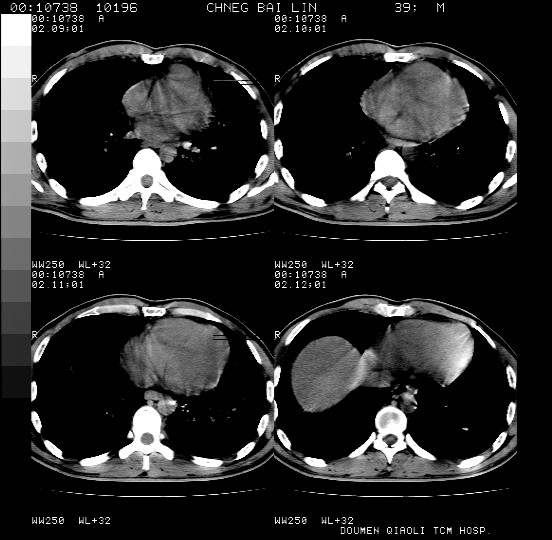

男,39岁。10天前自觉感冒,曾输液一次内容不详曾有吸毒史。现有咳嗽、咳痰胸闷。

双肺弥漫性网状、磨玻璃样病灶,边界不清。有吸毒史。首先考虑机遇性肺部感染。

双肺野蜂窝状结构及多发斑片状影,高度怀疑卡氏囊虫性肺炎

两肺弥漫分布的网状毛玻璃状阴影,边缘模糊不清,纵隔未见明显淋巴结肿大

诊断:机遇性肺部感染

鉴别诊断:1特发性肺纤维化,主要部位在两肺下叶胸膜下网状,毛玻璃状及蜂窝状阴影,临近胸膜增厚,该病征象不太符合